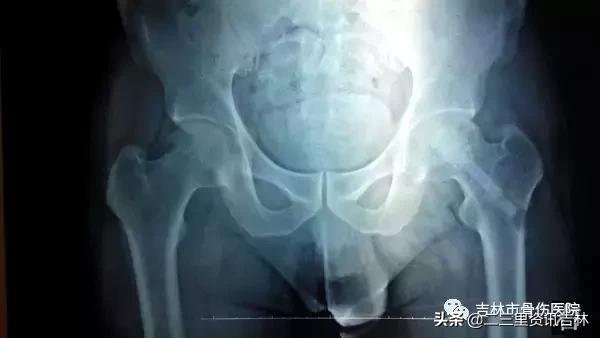

患者,男,33岁。双髋部疼痛伴活动受限半年,加重一周,经门诊医生查体、拍片以双侧股骨头坏死(II期)收入院。

术后1个月X线片(股骨头未出现塌陷)